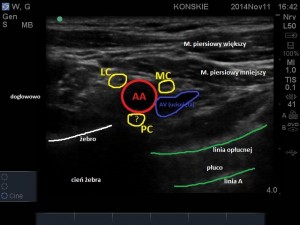

Wykorzystując dostęp LSICA liniową głowicę USG (u osób otyłych lub silnie umięśnionych konieczne będzie użycie głowicy convex) przykładamy w płaszczyźnie strzałkowej, tuż poniżej obojczyka i bezpośrednio przyśrodkowo w stosunku do wyrostka kruczego łopatki. W obrazie USG widzimy dwie warstwy mięśni: powierzchownie mięsień piersiowy większy, poniżej mięsień piersiowy mniejszy. Bezpośrednio poniżej mięśnia piersiowego mniejszego i jego powięzi (hiperechogeniczna linijna struktura) odnajdujemy naczynia pachowe (żyła pachowa, ulegająca kompresji leży zwykle poniżej tętnicy). Najczęściej na głębokości 3-5 cm, możemy rozróżnić trzy hiperechogeniczne pęczki splotu ramiennego ułożone wokół tętnicy pachowej: pęczek boczny, przyśrodkowy i tylny. Ułożenie pęczków względem naczynia jest bardzo zmienne osobniczo (patrz schemat ponizej), lecz najczęściej pęczek boczny leży dogłowowo w stosunku do tętnicy (pomiędzy godziną 9 a 12), pęczek przyśrodkowy doogonowo (pomiedzy 3 a 6 godziną) a pęczek tylny do tyłu od tętnicy ( pomiędzy 6 a 9 godziną). Głębiej w stosunku do struktur naczyniowo-nerwowych możemy uwidocznić opłucną oraz cień żebra. Należy pamiętać, iż poszczególne struktury nerwowe ulegają znacznemu przemieszczeniu podczas odwodzenia znieczulanej kończyny. Odwodząc kończynę pod kątem 90 stopni pęczki zbliżają się do siebie oraz przemieszczają się w stronę dogłowową.

- Sonoanatomia splotu ramiennego – dostęp LSICA